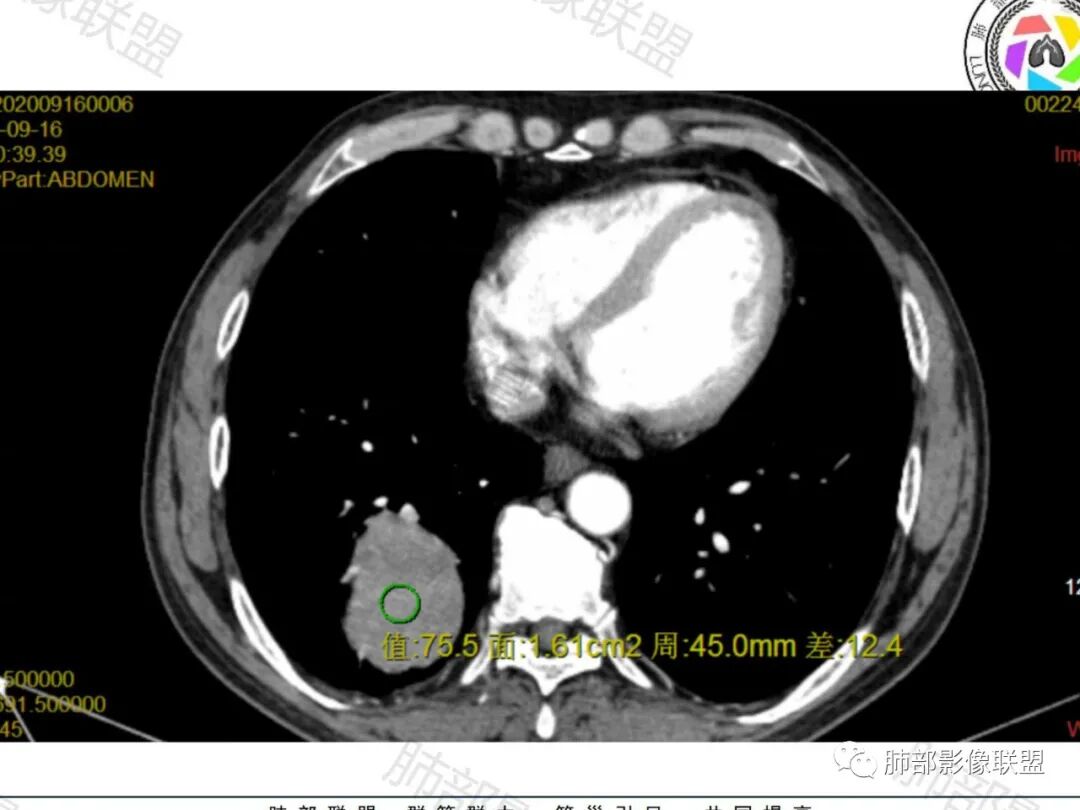

右肺下叶一类圆形肿块影,内缘边缘光滑,外缘边界模糊,可见磨玻璃影,整体以彭隆为主,部分边缘包绕支气管,平扫密度尚均匀,增强后不均匀强化,部分与膈肌黏连,临床,62岁男性,无症状,考虑恶性:腺癌,鳞癌,神经内分泌癌,肉瘤

老年人,偶然发现,右肺下叶类圆形软组织占位,密度较均匀,病灶边缘光滑,无毛刺分叶,支气管血管受挤压向外移位,增强病灶强化较均匀。考虑恶性肿瘤,外向内生长,肉瘤,肉瘤样癌,癌肉瘤,其次神经内分泌癌。

老年男性,右肺下叶软组织肿物,整体外形光整,周围组织推挤,可见血管贴边,貌似又有血管进入,整体强化均匀,考虑良性可能大,硬化性肺细胞瘤?鉴别sft

老年男性,偶然发现,说明平时没有症状,边缘光整,血管贴边,整体强化均匀,倾向于良性或者低度恶性(PSP?类癌?)

老年男性,肿瘤标志物高,右肺占位,边界清楚,内部密度均匀,坏死不明显,无明显分叶,血管贴边,考虑PSP,老年男性,肿块大,需鉴别恶性,肉瘤样癌?高分化鳞癌?

男性,62,胆结石入院胸部CT偶然发现占位。肿标稍增高,右肺下叶胸膜下肿块,边缘尚清,密度较均匀,增强明显强化,血管贴边,空气新月征?静脉期可见低强化区,首先考虑PSP,鉴别肉瘤样癌及神经内分泌肿瘤

老年男性,右肺下叶肿块,边缘光整,血管贴边,部分血管进入,整体强化尚均匀,考虑大细胞癌,鉴别PSP、SFT

右肺下叶类圆形软组织肿块,病灶边缘光滑,无明显毛刺分叶,支气管受压推移,血管贴边,部分血管进入病灶,增强病灶强化不均匀,内可见低密度,病灶与右侧膈肌分界不清,考虑神经内分泌肿瘤,大细胞癌。鉴别PSP

老年男性,肿瘤标志物高,右肺下叶类圆形肿块,宽基底与胸膜相连,边缘光整,密度均匀,周围气管及血管受压推移,延迟强化,其内见纤细血管,似有小低密度灶,首先考虑间叶组织恶性肿瘤,良性平滑肌瘤、纤维瘤不除外

患者中老年男性,检查发现右下肺占位。查肺癌标记物稍有升高。血常规白细胞计数稍降低。胸部CT:右肺下叶后基底段类圆形肿块,边缘光滑,边界清楚,周边见气管受压扩张,增强轻度强化,内见点状低密度影,见血管贴边。综合考虑良性过低度恶性病变,PSP可能,其它恶性肿瘤待排。

支气管,血管均受压推移,类圆形占位,无分叶,无毛刺,光滑表面,明显均匀强化,倾向于psp,鉴别错构瘤,肉瘤,肉瘤样癌,类癌等神经内分泌肿瘤,转移,imt。

老年男性,右肺下叶软组织肿块,边缘光滑,血管和支气管贴边,肿块与膈肌分界不清,增强后不均匀强化,可见点片状低密度影,考虑良性或低度恶性肿瘤,psp,神经内分泌肿瘤

右肺下叶大肿块,血管贴边,部分小分支进入肿块内,密度略欠均匀,边缘总体光滑,支气管关系不明确,老年人,总体考虑恶性,nse高,首先考虑神经内分泌癌,鉴别肉瘤,转移瘤

右下肺大团块,边界较清,病灶内有血管影,小灶低密度,胸膜下脂肪清晰,需要薄层确定肺血管有没穿行,疾病谱:神经内分泌癌(大 类),SFT,PSP,肉瘤样癌,间叶肿瘤,考虑神经内分泌癌(大 类)>sft>psp>肉瘤样癌

老年男性,NSE高。右肺下叶软组织肿块,平扫密度均匀,增强后不均匀强化,其内似可见小血管影。肿块边缘光滑,无分叶无毛刺,血管和支气管贴边。考虑神经内分泌肿瘤,鉴别:psp

老年男性,检查发现右下肺占位。CT:右肺下叶一类圆形肿块影,膨隆,无分叶,边缘基本光滑,近端支气管推挤狭窄,与胸膜夹角为锐角,增强见不均匀强化,未见坏死,近端见血管贴边,胸壁脂肪间隙清楚。考虑良性病变——PSP可能性大。鉴别神经内分泌癌、肉瘤、SFT。

右肺下叶软组织肿块,边缘光滑,临近血管受压变形且增粗,增强后见斑片状低强化区,界不清,实性部分见条状血管影,边缘光滑,考虑PSP可能,肿块与支气管关系不密切,腺癌,腺鳞癌不符合,肿块内增强后血管走形自然,间叶组织起源肉瘤不符

有意思的病例,男性,右肺下叶肿块,强化中等,血管贴边,肿标高,考虑低度恶性肿瘤,神经内分泌肿瘤,类癌最可能,别的感觉都要往后放,PSP,我三十五例病例,男性只有3例,比例太低了,而且强化幅度也偏低,而且肿瘤标志物好几个高的,只敢放第二位了

右肺下叶肿块,呈外带大内带小的椭圆形改变(内带受支气管及血管挤压原因),边缘光滑,无分叶毛刺,支气管受压,增强后,均匀延迟强化,动脉期见血管贴边,静脉期内部瘤样血管强化区,相邻胸膜无侵犯,纵隔无淋巴结肿大,符合PSP,不鉴别。

老年男性,肿瘤标志物高,右下肺占位性病变,密度均匀,其内无明显坏死,均匀强化,无毛刺分叶,考虑硬化性肺细胞瘤,鉴别肉瘤样癌

老年男性,右肺下叶肿块,边界光滑,血管贴边,部分小分支进入,肿块内可见增粗血管,肿瘤指标偏高,总体考虑恶性,不典型类癌?大细胞癌?鉴别PSP。

胸部CT:右肺下叶一类圆形肿块影,边界清楚,大部分边缘光滑、外缘边界模糊,邻近支气管推移、血管贴边,病灶内可见分枝状血管,平扫密度尚均匀,增强后大部分均匀延迟强化,部分与膈肌黏连、尾征?考虑:类Ca>PSP>SFT。鉴别肉瘤样Ca,CD等。

肿块位于周围(起自细支气管呼吸道上皮),均匀膨胀生长(符合良性的生长特点),病灶内部大部分密度较均匀,部分小低密度不强化区(囊变),增强强化较明显,边缘血管增粗贴边,临近支气管受压,支持PSP。

刷新了我的认知,这个类癌这么大一点没分叶,而且支气管血管推移那么明显。而且影像上没看到支气管截断,从病理来看,也确实没有累及支气管,

工作中肯定要鉴别类癌的,主要也是这两个鉴别,而且有时候确实比较难,但这个支气管推移情况和血管情况确实让我比较肯定是PSP,结果太笃定,错了。😂

KI67  --1%   核分裂相很低

psp 女男比例4-5:1,一般小于3CM,这个是有点大,这个好像要8cm以上了